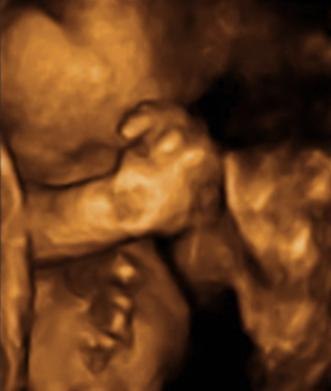

Så blev det endelig vores tur til scan igen, nøj det var jo bare vildt!!!

Orhh....hvor er mors lille <---- ( ? ) klump dejlig, nøjh nogen dejlig kinder.

Han blev målt til at jeg skulle være 1 uge længer fremme, men det kunne snyde op til 10% sagde hun.

Vægten sagde 1193.g